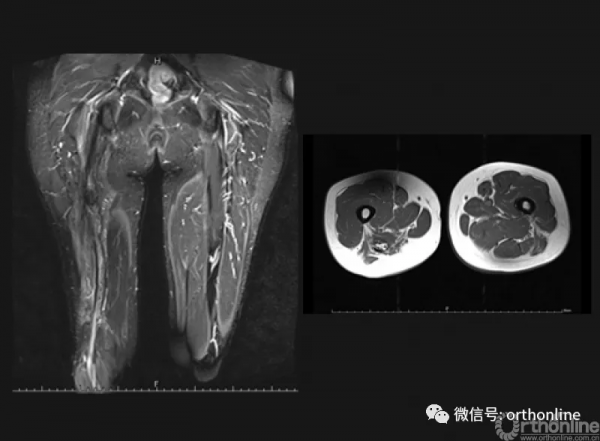

患者女,23歲,左大腿複發性硬纖維瘤,觀察期間腫瘤進展。

術前磁共振提示腫瘤包繞坐骨神經與膕血管。周圍肌肉組織行廣泛切除,坐骨神經與膕血管R2切除後行三明治隔離手術,術後55.5月隨訪過程中,補片隔離區域未見覆發。

術前磁共振影像